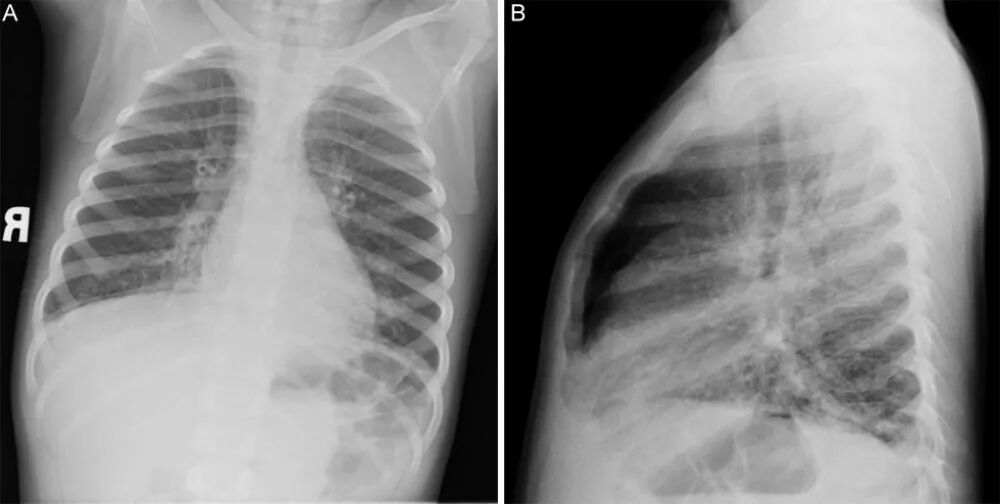

2.影像学特点  临床研究表明,重症腺病毒肺炎患儿肺部影像学表现特点如下:双肺见大片实变影,部分融合成片,边缘模糊;实变可呈节段性,多肺叶受累,可融合成大叶性实变,内可见支气管充气征;病变多以肺门为中心分布,而外带病变相对较少;部分病例以肺间质改变或间实质改变为主,表现为支气管血管相对增多、模糊,其间可见沿支气管分布的细小点片状影;部分病例在疾病后期出现闭塞性细支气管炎、慢性肺病表现,如马赛克征象、细支气管壁增厚、扩张等。以上影像学特点均提示重症腺病毒肺炎患儿肺部病变较重,易遗留肺部后遗症。

6个月后高分辨率CT随访发现肺纤维——轻度支气管扩张,左下叶基底段肺大泡。